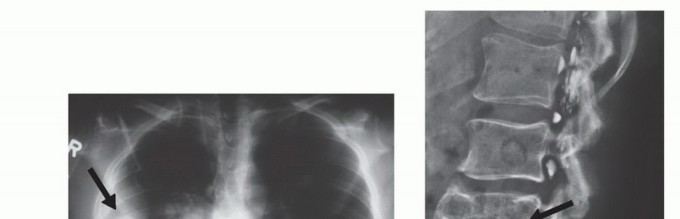

Imaging and Staging

Prior to any tissue sampling, complete local and systemic imaging must be obtained. This typically includes high-quality orthogonal plain radiographs of the affected bone, and a contrast-enhanced MRI of the entire anatomic compartment (joint-to-joint) to assess tumor volume, neurovascular proximity, and the presence of skip metastases. Staging studies, including a CT of the chest to rule out pulmonary metastases, and potentially a whole-body bone scan or PET-CT, should be completed or scheduled prior to the biopsy.

Furthermore, aggressive high-grade sarcomas may shed cells that break through the pseudocapsule and travel along longitudinal tissue planes to form metastases within the same anatomic compartment, entirely separate from the primary mass. These are termed "skip metastases." By definition, these are locoregional micrometastases that have not passed through the systemic circulation.